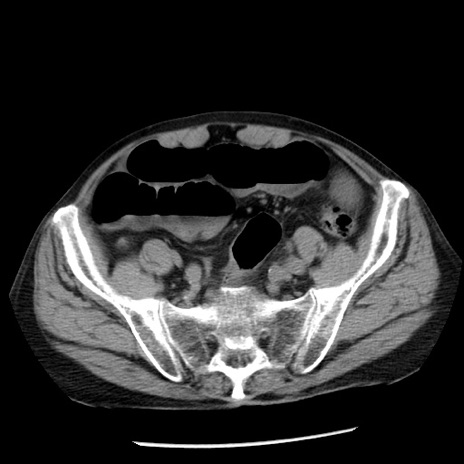

症例26(横断像)

【症例】80歳代男性

【主訴】嘔吐

【現病歴】昨晩2回嘔吐あり、今朝になっても嘔吐あり。来院。

【既往歴】胃潰瘍

【身体所見】意識清明、BT 37.6℃、BP 166/95mmHg、HR 100bpm、SpO2 97%、腹部:平坦・軟、腸蠕動音聴取良好、圧痛なし。

【データ】WBC 21900、CRP 1.46